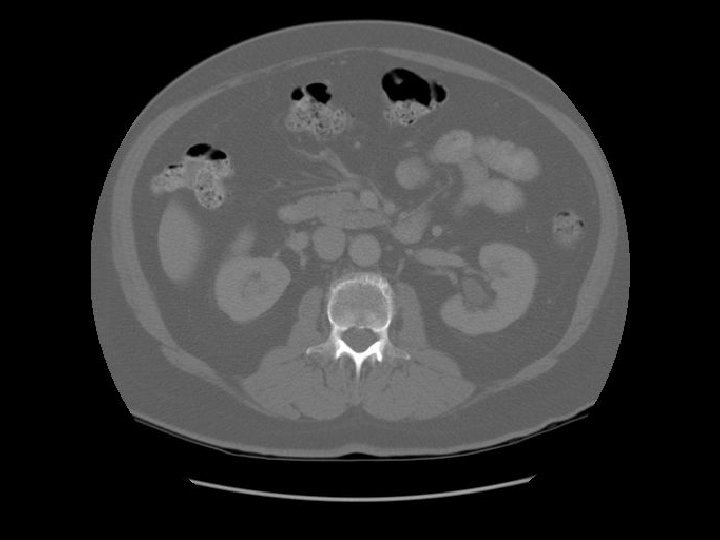

Kidney Right Kidney